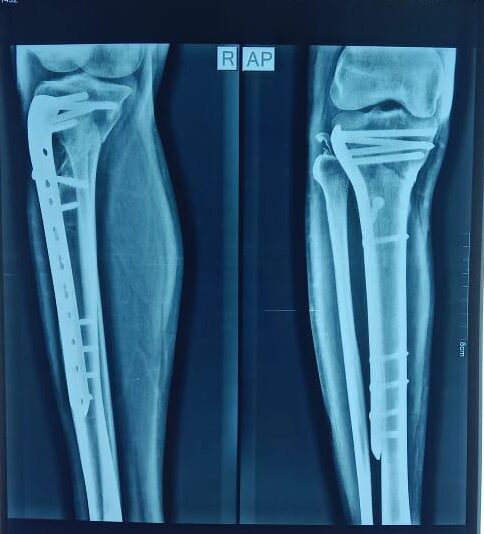

Moments That Mark Meaningful Recovery

Witness real patient transformations at The Ortho Clinic through images that reflect successful treatments and restored mobility.